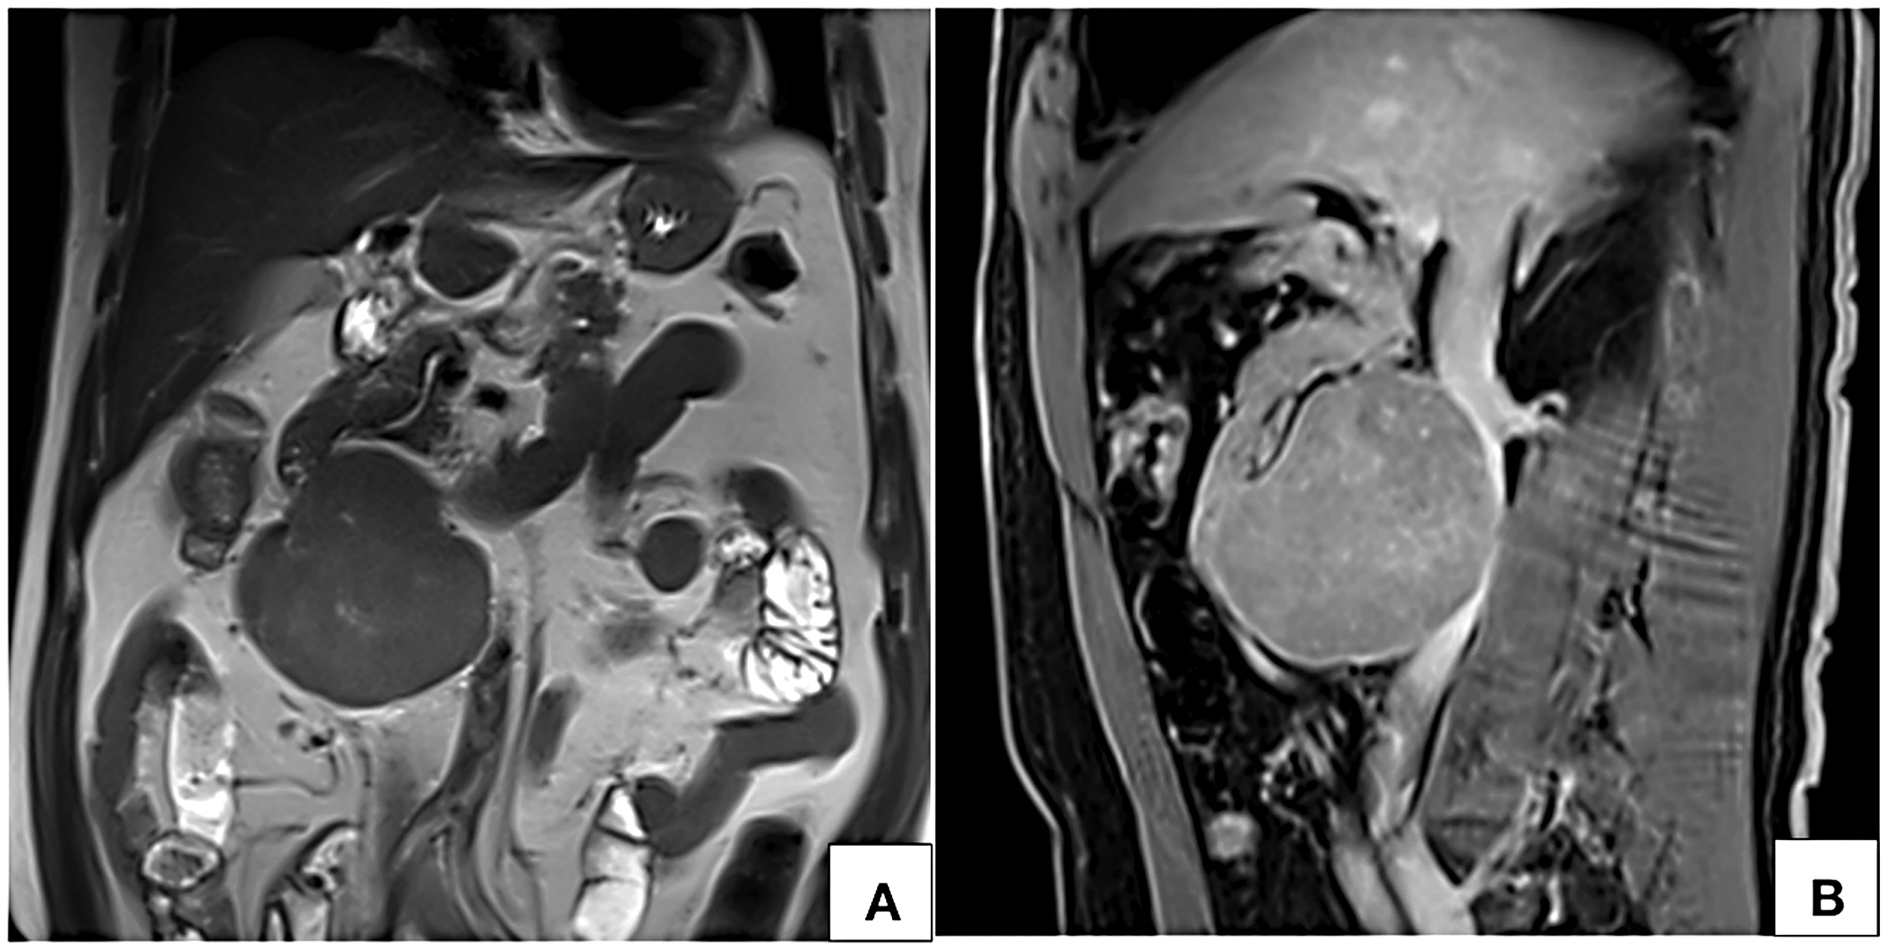

lumen at the site of maximum contact. However, proximal and distal segments of the inferior vena cava showed normal contrast opacification. Medially, the lesion was in relation to the abdominal aorta. Second and third part of duodenum and head of pancreas were displaced anterosuperiorly. Magnetic resonance imaging (MRI) showed a homogeneously enhancing circumscribed lesion in the retroperitoneum on right side of midline appearing isointense on T1W, hyperintense on T2W showing restricted diffusion. Few cystic areas were seen within the lesion. On prone imaging, the lumen of inferior vena cava was still imperceptible at the site of maximum contact. No obvious intraluminal extension was seen. Whole body positron emission tomography CT revealed mild FDG uptake with a maximum standard uptake value (SUVmax) of 4.1. No distant metastases were found.

One of the important imaging feature for characterization of retroperitoneal tumors is the relationship with IVC. Webb Em et al [27] undertook a retrospective analysis of 13 cases of retroperitoneal tumors to study the performance of four different radiological signs in differentiating LMS of IVC from other primary retroperitoneal tumors. Radiological signs that were studied are positive embedded sign, negative embedded sign, imperceptible IVC sign and tumor in lumen. They observed that imperceptible IVC lumen at the site of maximum contact is highly predictive of a IVC origin. Case described in this manuscript had the imaging feature. Prone imaging can be of diagnostic utility in demonstrating primary origin from IVC in patients with predominantly extraluminal lesion. On prone imaging, these tumors show persistent contact with the wall of IVC or persistent nonvisualization of the lumen of IVC. Tumors with predominant extraluminal component commonly occur in anterior relation to the IVC and towards the right side of midline [9-11, 17, 19]. However, tumors originating posteriorly from the IVC have also been reported [5, 14].

On MR imaging LMS of IVC appears hypo- to intermediately intense on T1W and hyperintense on T2W [10, 18, 26]. Due to their malignant nature, these tumors also show diffusion restriction [18]. Similar signal characteristics were observed in our case also.